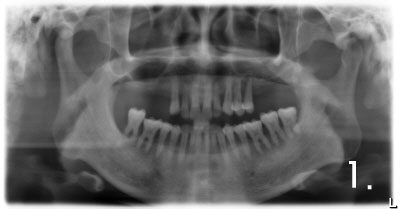

There is not enough bone to place implant on upper and left side.

Performed sinus graft more than 90% of bone required to place implant

Placing implant in bone graft site

Implant crown was fabricated